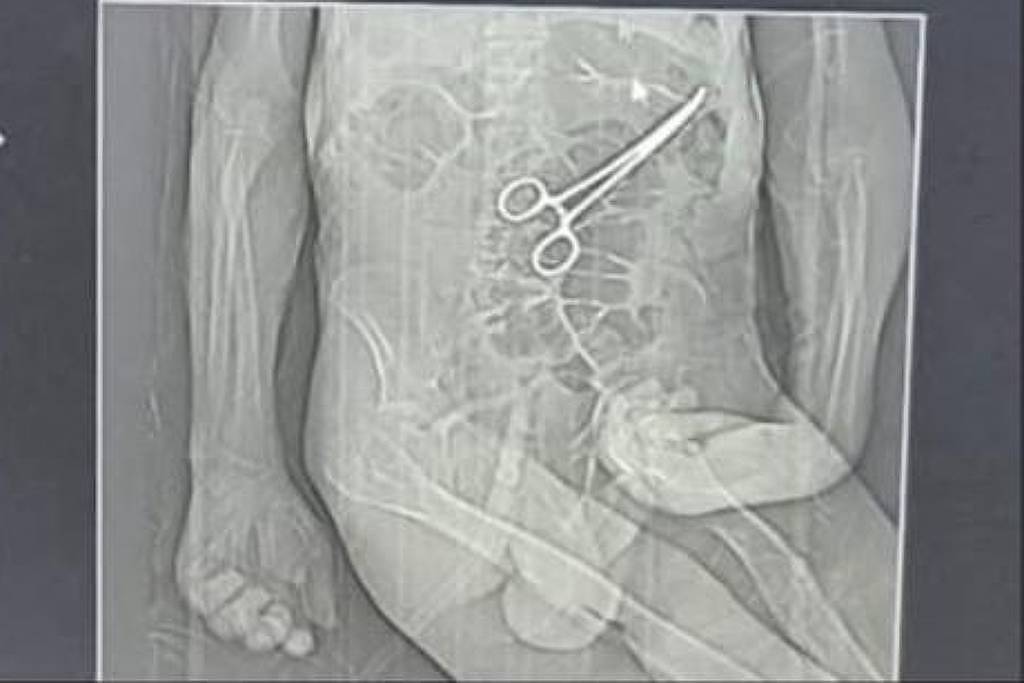

Família acusa hospital de esquecer pinça em corpo de idoso morto na véspera do Natal em MG

FOLHAPRESS A família de um aposentado que morreu na véspera do último Natal em João Pinheiro, no noroeste de Minas Gerais, acusa médicos do hospital municipal de esquecerem uma pinça no abdômen do idoso durante uma cirurgia feita semanas antes do óbito. A Secretaria Municipal de Saúde de João Pinheiro reconheceu, em nota, que realizou um procedimento para retirar um "corpo estranho na cavidade abdominal". Contudo, afirmou que o objeto não causou perfurações em órgãos do paciente. A nota afirma também que o idoso deu entrada na unidade "em estado clínico extremamente debilitado". Declarou ainda ter instaurado uma sindicância para apurar o caso. Manoel Cardoso de Brito, 68, morreu no dia 24 de dezembro no Hospital Municipal Antônio Cordeiro Valadares após ser submetido a duas cirurgias. A primeira internação ocorreu no dia 4 de dezembro, quando o idoso passou mal em casa. Segundo o município, ele apresentava "vômitos com sangramento, associado a sequelas neurológicas importantes e rebaixamento do nível de consciência". Ele foi transferido da UPA (Unidade de Pronto Atendimento) da cidade para o hospital, onde realizou a primeira cirurgia. Após a cirurgia, o paciente voltou a apresentar sintomas graves, o que levou à realização de novos exames. Nesse momento, uma tomografia identificou, segundo a secretaria, "um corpo estranho na cavidade abdominal". A nova cirurgia foi realizada em 11 de dezembro. Manoel ficou internado até o dia 24, quando morreu. A família afirma que o hospital não informou sobre a existência do "corpo estranho" identificado no abdômen do paciente. Segundo um dos filhos, que registrou um boletim de ocorrência na Polícia Civil, a equipe médica relatou que o procedimento foi realizado para a retirada de dreno e pus. Os parentes também afirmam que só souberam do que de fato havia ocorrido por meio de uma reportagem de uma rádio local, quando tomaram conhecimento da imagem de uma tomografia indicando uma pinça no abdômen de Manoel. O advogado da família, Iuri Furtado, afirma que a família busca "a verdade dos fatos que envolvem o falecimento". "Desde o primeiro momento, nosso compromisso é com a justiça, a transparência e a responsabilização, sem pré-julgamentos, mas com absoluta seriedade diante do quadro que se apresenta como um possível erro médico", afirmou o advogado, em nota. A secretaria afirma que a direção do hospital, ao tomar conhecimento do fato, "adotou imediatamente todas as providências cabíveis, incluindo a notificação de evento adverso, a apuração das barreiras de segurança, o reforço dos protocolos de segurança do paciente, bem como a notificação à Anvisa, para instauração de sindicância e apuração rigorosa dos fatos". "O município manifesta sua solidariedade aos familiares e reafirma que permanece à disposição para prestar toda a assistência necessária, bem como para fornecer esclarecimentos adicionais, sempre pautado pela ética, responsabilidade e compromisso com a saúde pública", afirma a nota da secretaria.